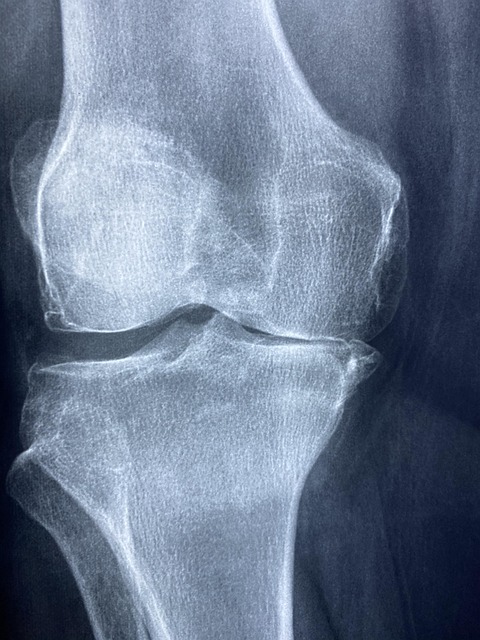

- 류마티스내과 진료를 통해 문진, 관절 진찰, 혈액검사(류마티스 인자, 항CCP 항체 등), X선·초음파 검사를 시행합니다.

- 조기에 진단하면 관절 변형과 손상을 상당 부분 막을 수 있고, 통증과 피로를 줄이며 일상생활을 유지하기 쉬워집니다.